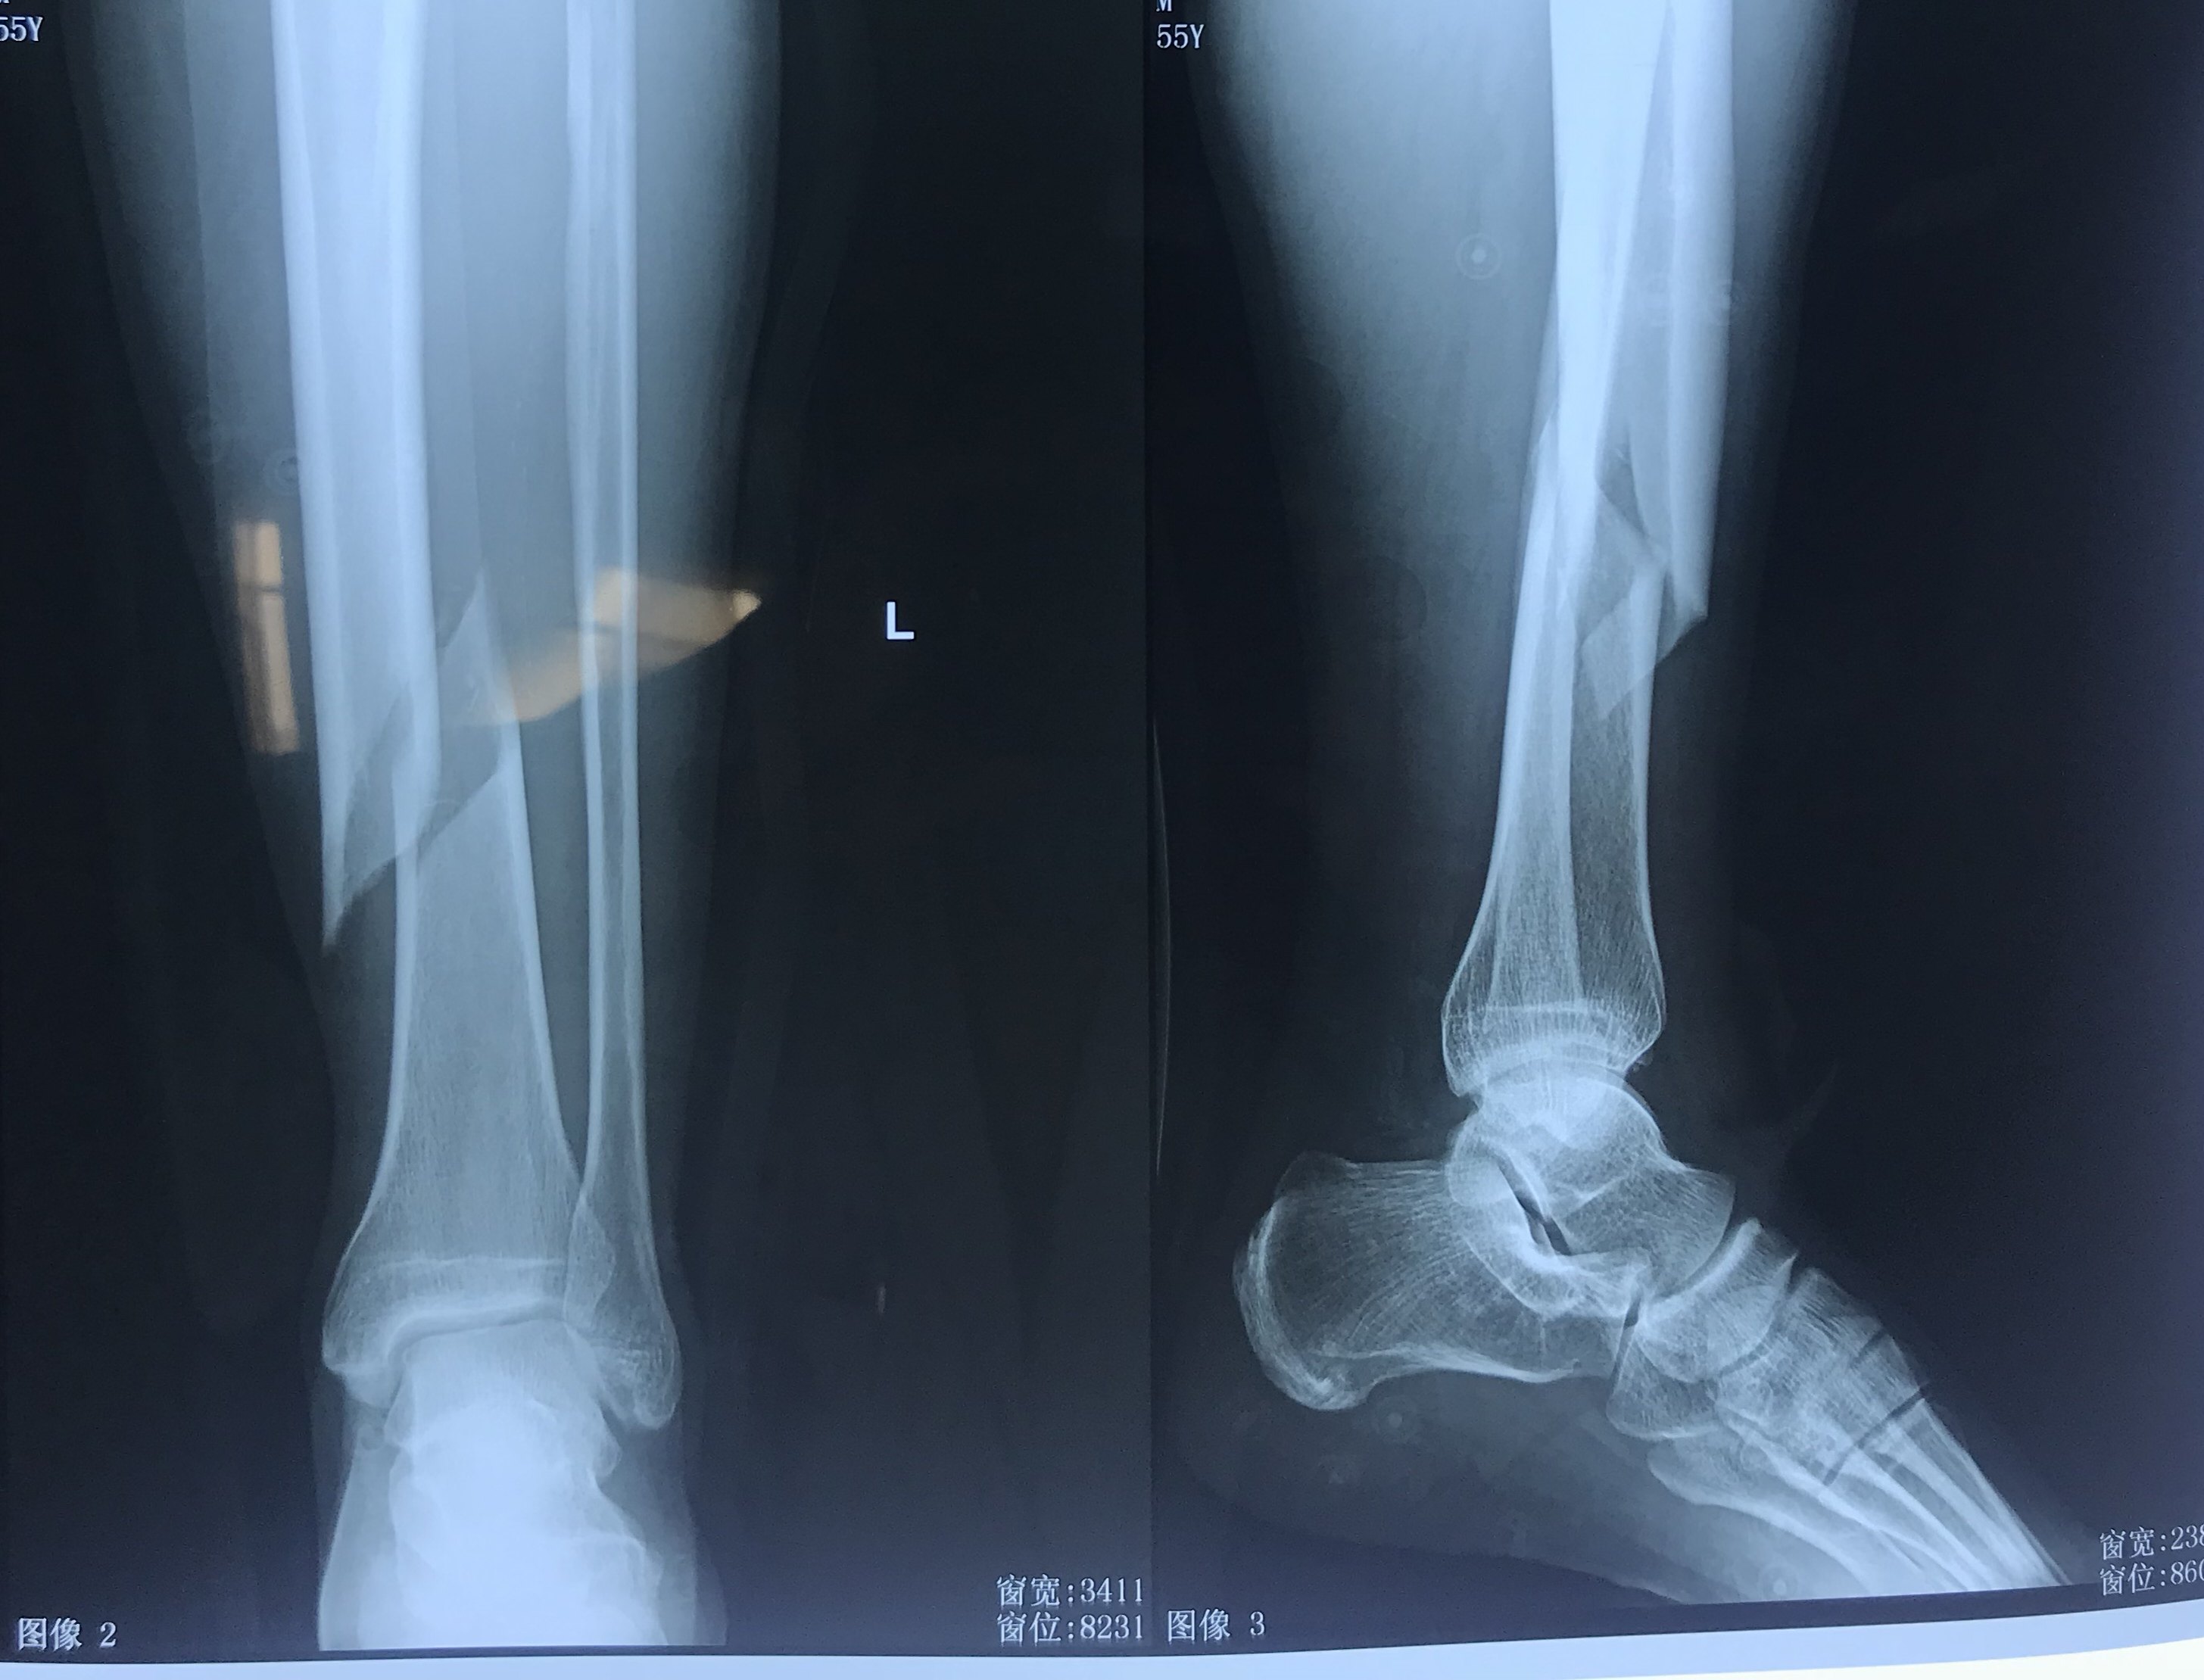

脛骨骨折包括脛骨幹骨折和脛骨平臺骨折。脛骨平臺骨折是膝關節創傷中最常見的骨折之一。脛腓骨幹骨折在全身骨折中約佔945%。10歲以下兒童尤為多見。 檢查 x線片檢查有助於骨折和骨折型別的診斷。 診斷脛腓骨骨折在長管狀骨 骨折中最常見。 脛腓骨幹骨折 脛骨淺居皮下,缺乏肌肉附蓋,故骨折後極易被骨折斷端穿破皮膚。 多見兒童和青壯年。多為直接暴力所致。若發生在中下段,易引起延遲癒合或不癒合。 重定不好會產生創傷性關節炎。傷害レポート~脛骨骨折~ エム・エス・マイスターには様々な痛みを抱えた方が来院されます。 今回は今年の7月に脛骨骨折をした藤枝東高校サッカー部の選手が復帰をした経過を掲載します。 受傷は7月6日の公式戦の接触プレーで受傷しています